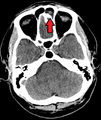

![]() | |

يشير السهم إلى منطقة الالتهاب في جيوب الفك العلوي في الجانب الأيسر من الوجه. لاحظ أن المنطقة التى يشير لها السهم ليست شفافه لقلة الهواء فيها، مما يشير إلى امتلائها بالسوائل بالمقارنه مع الجانب الآخر من الوجه. | |